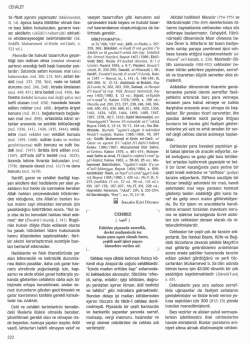

Birlikte Etkilesimli Yonetim Dunyanin Damina Seyahat Yeryuzunun En Saglikli Sporu Dunya Tip Ve Saglik Oyunlari Muayenehane Pratiginde Anestezi Pdf Free Download

Birlikte Etkilesimli Yonetim Dunyanin Damina Seyahat Yeryuzunun En Saglikli Sporu Dunya Tip Ve Saglik Oyunlari Muayenehane Pratiginde Anestezi Pdf Free Download

Birlikte Etkilesimli Yonetim Dunyanin Damina Seyahat Yeryuzunun En Saglikli Sporu Dunya Tip Ve Saglik Oyunlari Muayenehane Pratiginde Anestezi Pdf Free Download